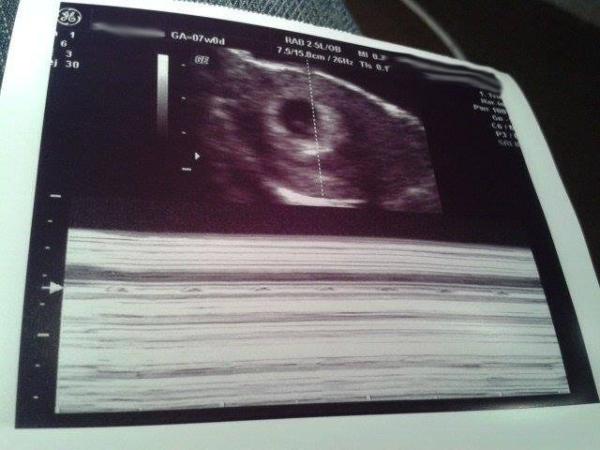

Dated as 6+4, so 2 days behind what I'd thought originally, but I can live with that. Strong heartbeat, but baby kept wanting to hide (I blame the father, such an introvert!), so measured in at 7mm. This brings my due date to the 16th Dec - eeeek! :D

Picture attached is scan of heartbeat, the line with the arrow shows it as it throbs - could see it flicering stongly on the screen __